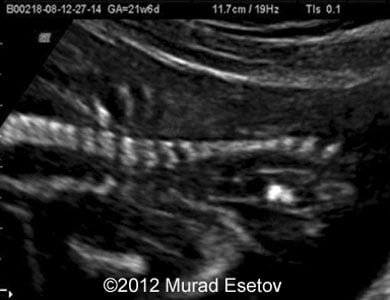

We report a case of a 17-year-old woman (G1P0) sent to our office at 21 weeks and 6 day of gestational age. Her medical history was unremarkable. During the ultrasound examination we discovered a bony septum arising from the vertebrae at the level between 10th and 12th thoracic vertebrae and spina bifida aperta. There was some widening of the spinal canal as well. There was cranial signs of spina bifida (Arnold Chiari ruled) and clubfoot.

Images 3, 4: The image 3 shows a transverse scan of the fetal head with enlargement of the lateral cerebral ventricles. The image 4 shows a 3D rendering of clubfoot.

Image-3

Image-4